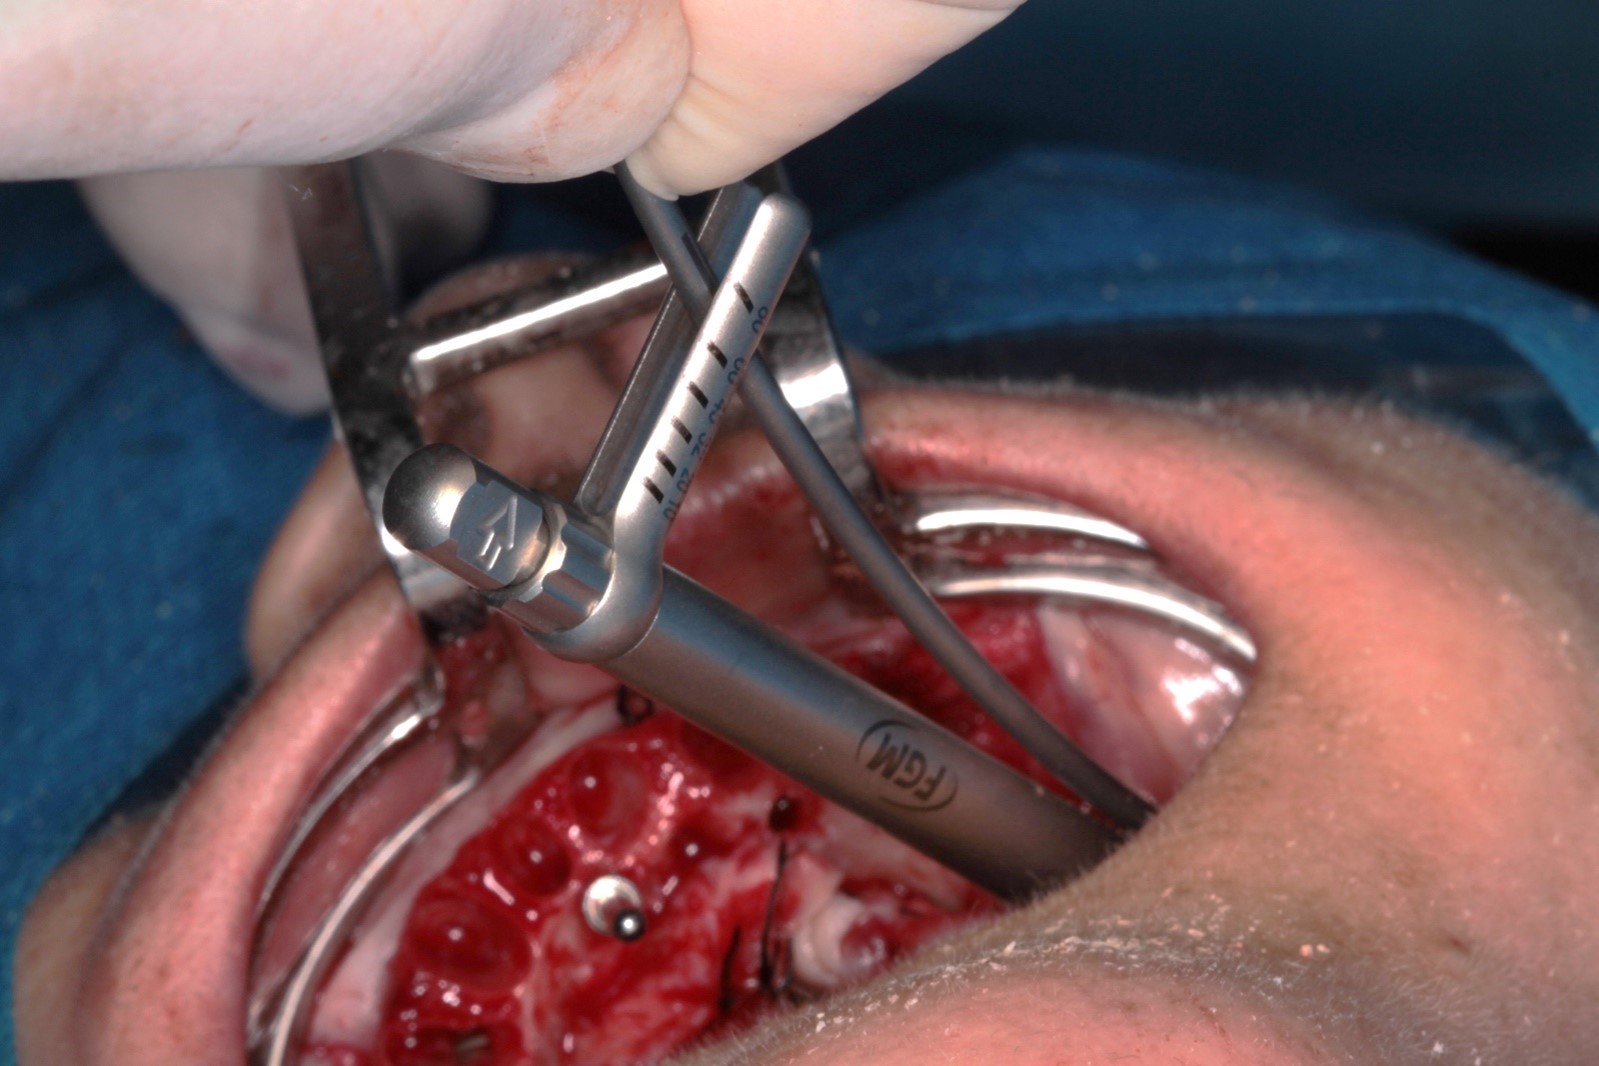

FIG. 07 – Torque de 80N obtido no implante distal.

FIG. 08 – Instalação dos mini pilares angulados de 30 graus nos posteriores e retos nos anteriores.